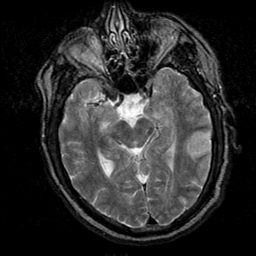

Subacute Stroke, overlay -- Slice #10

[Home][Help][Clinical] Slice 10